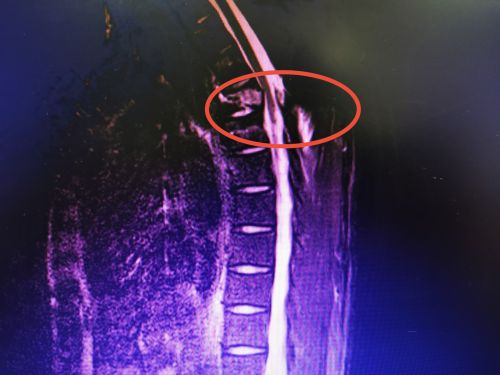

翁先生术前影像显示:胸4椎体及附件骨折伴骨髓水肿,继发骨性椎管狭窄、后方韧带复合体撕裂。

不要以为只有老年人运动协调能力退化不经摔,年轻人也不例外。株洲29岁的翁先生从3米高的杨梅树上坠落,胸背部着地,胸背呈持续性刺痛,急诊以“胸椎爆裂性骨折”收入省人民医院脊柱外科。完善术前相关检查后,沈雄杰主任医师等为他在全麻下进行胸椎后路复位植骨内固定术。术后,患者生命体征平稳,四肢肌力正常,转入普通病房继续治疗。